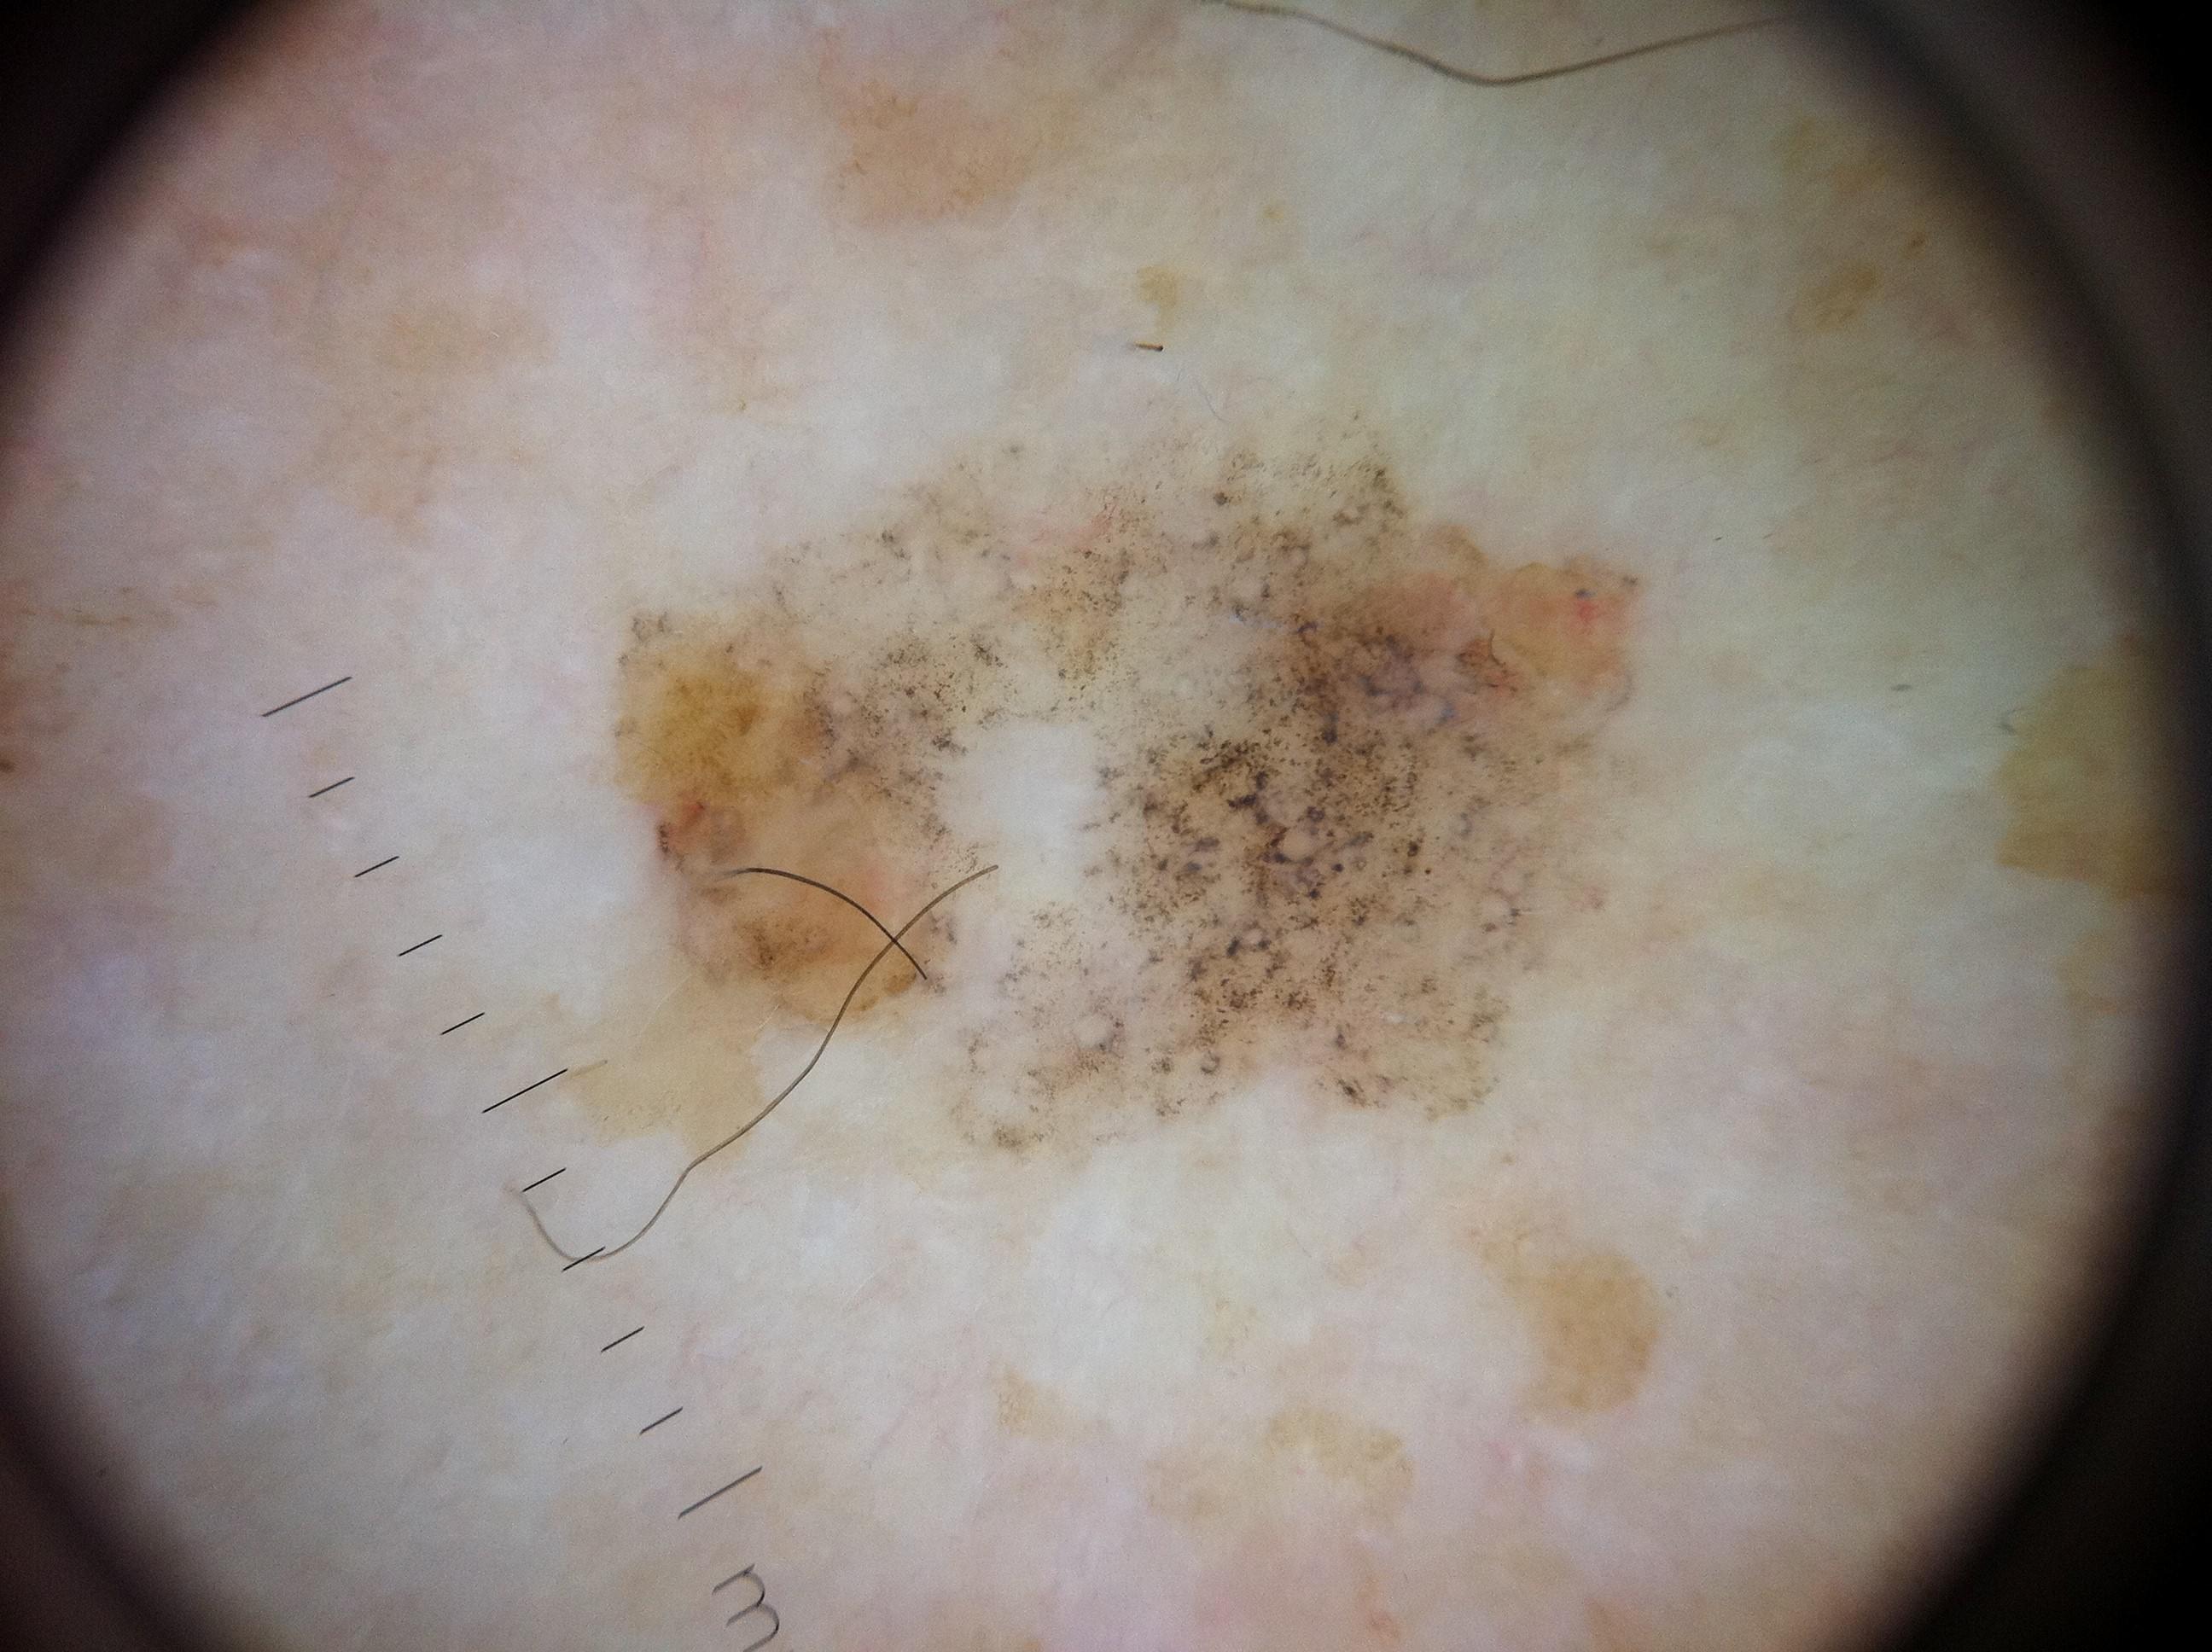

Biopsy-confirmed melanocytic and non-melanocytic skin lesions. This dataset includes over 500 melanomas. Many images have polarized and contact variants.